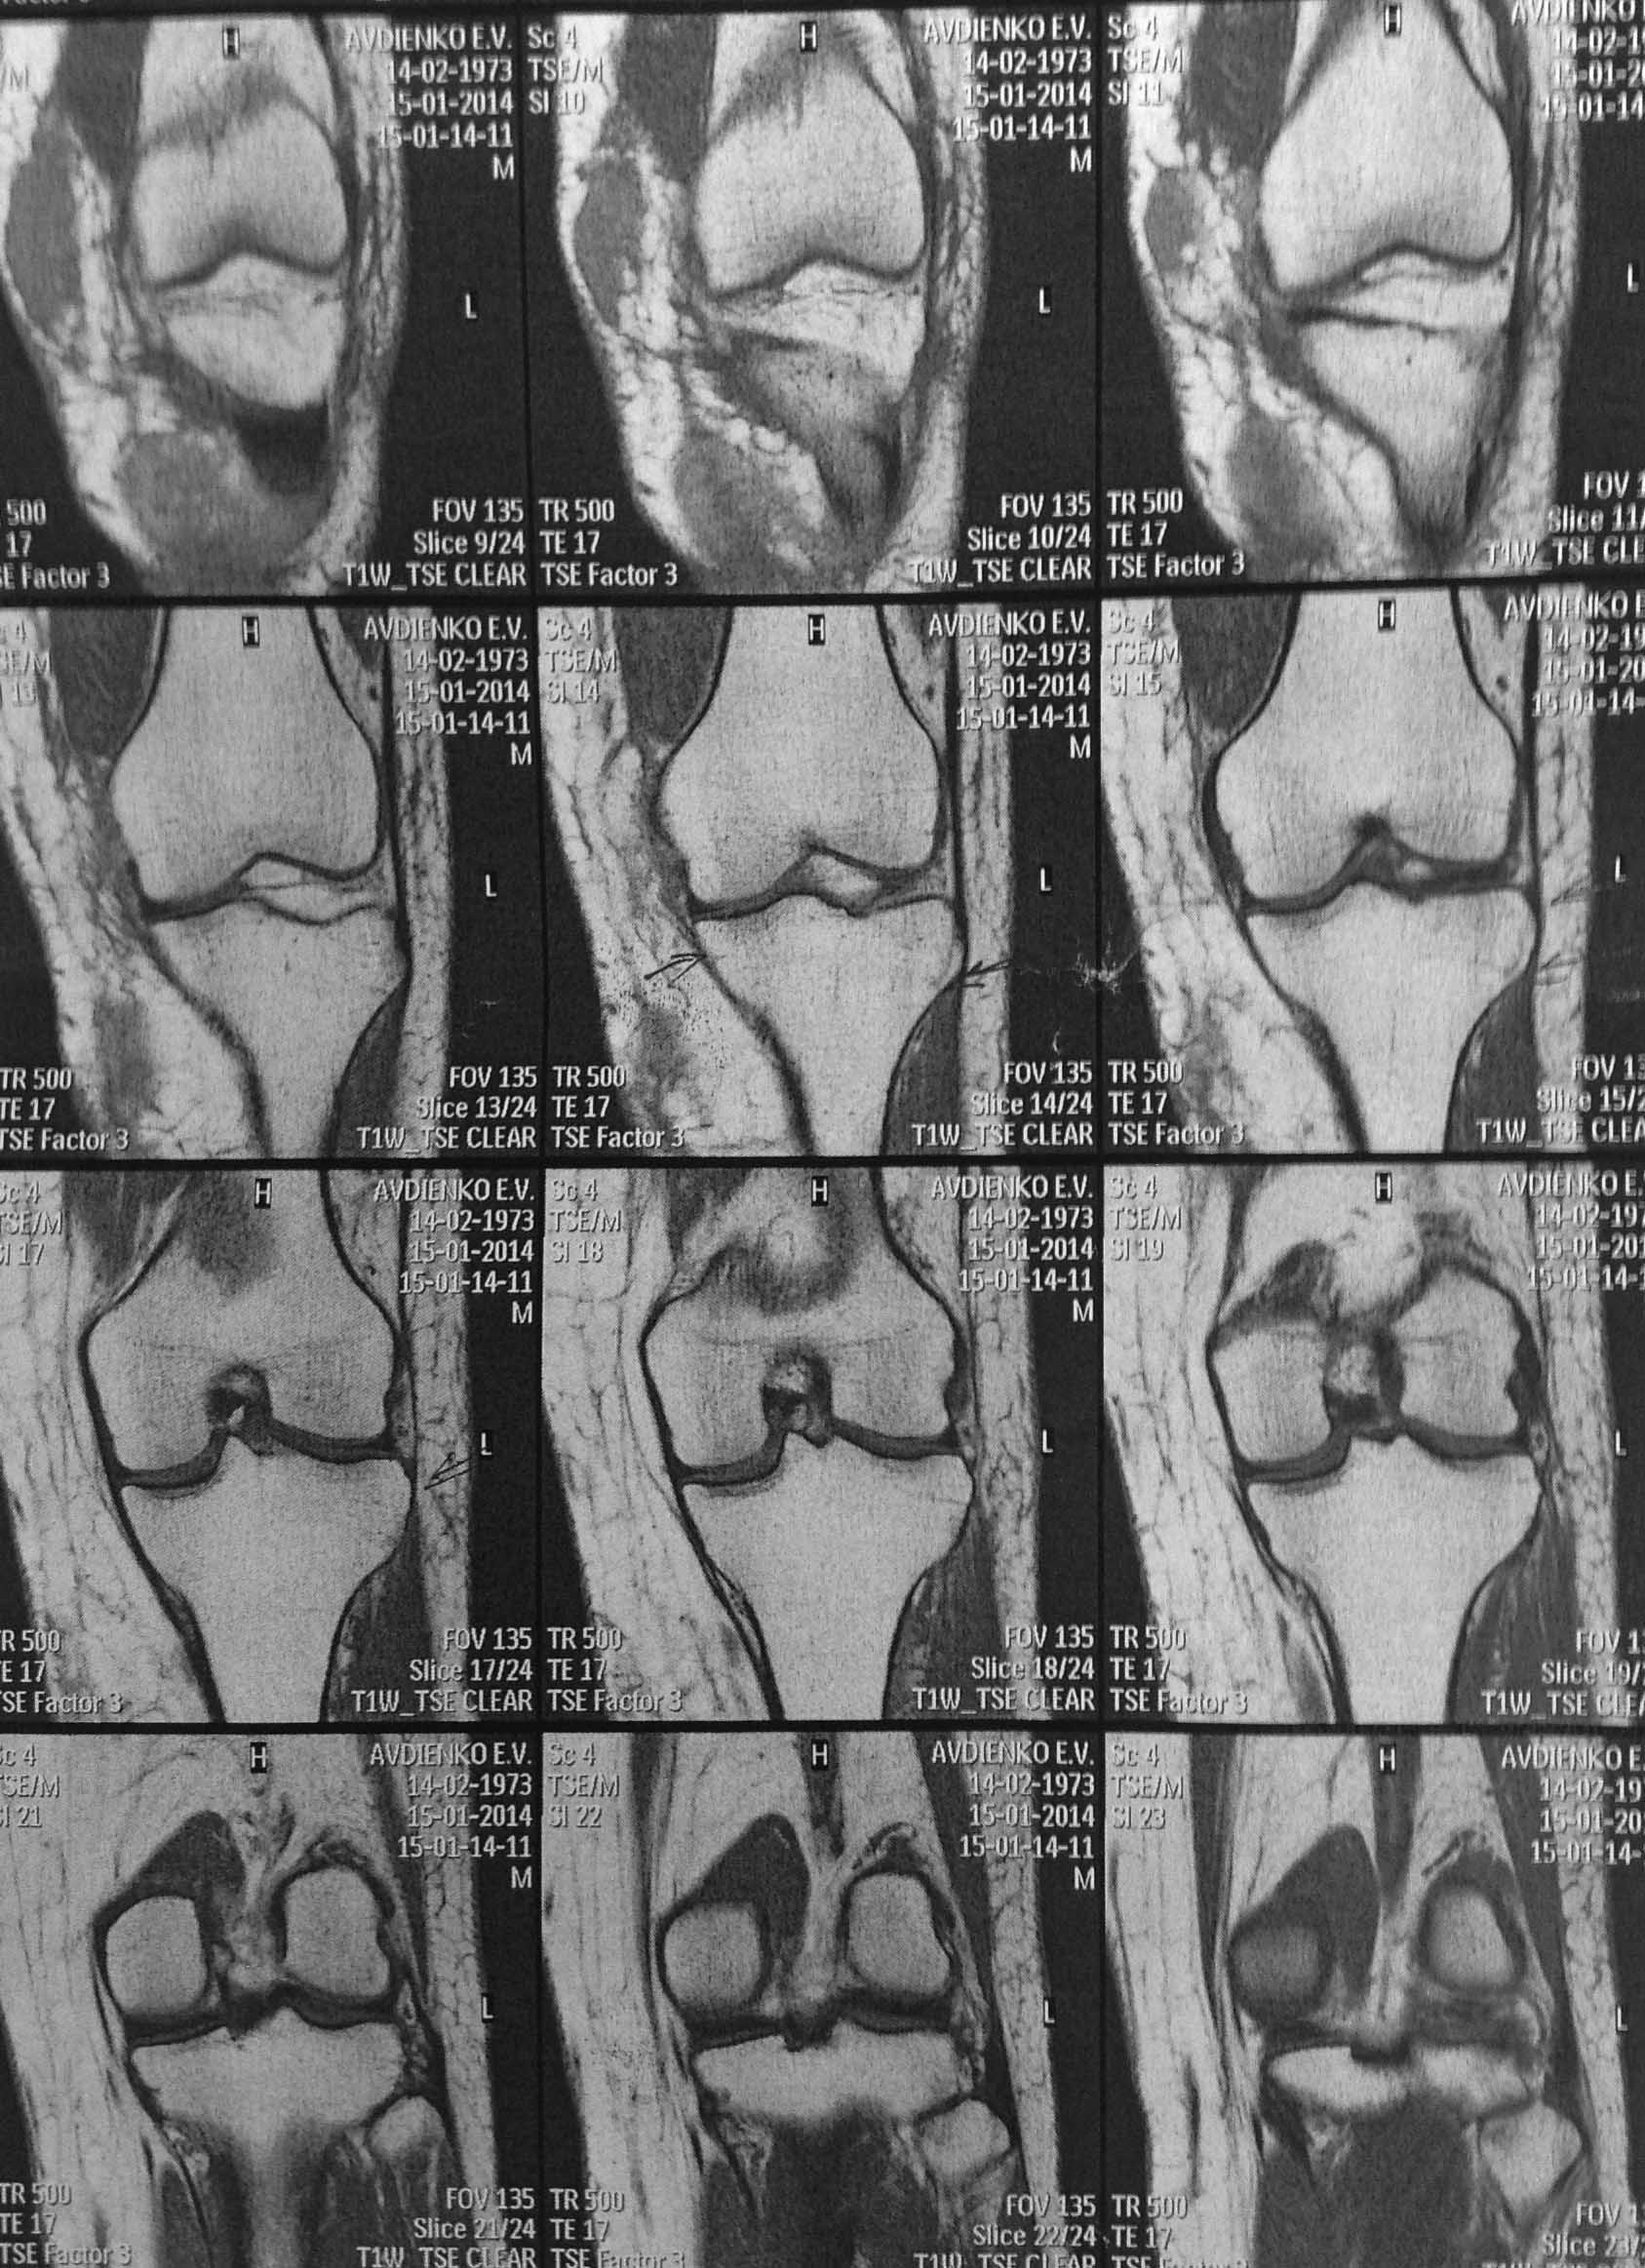

Уважаемые коллеги? Понимаю несуразность поста, но все же. Пациентка Ж 40 лет, травма ДТП 29.12.13, по месту получения травмы вскрыта межмышечная гематома, иммобилизация тутором.

Объективо- движения в коленном суставе 0/0/0, связочный аппарат стабилен. НО САМОЕ консультация профессора ( дама не из простой семьи) - и вердикт - оскольчатый внутри суставной перелом наружного мыщелка большеберцовой кости и лечение- 3 месяца постоянный тутор. Меня чуть на ноль не умножали, что я пропустил перелом в таком важном месте. Коллеги!!!!!! А был ли мальчик, вглядитесь пожалуйста и вынести решение!!!!!!!

Можно заподозрить минимальную импрессию наружного мыщелка, но и то только когда начинаешь вглядываться...скорее всего спор может разрешить только артроскопия коленного сустава.

я тоже перелома не вижу, ровно как и других серьезных повреждений

То, что указано стрелками, называется в рентгенологии "посттравматический отек костного мозга"

Отек костного мозга был бы лучше виден в Т2-режиме, а там вообще ничего нет / или тех срезов где что-то есть не представлено.

Кроме того, стрелочки на кортикал направлены, а не в костный мозг:)

ТО, что помечено стрелочками - это вообще ничто, таких стрелочек можно на любом скане с десяток нарисовать и щеки раздувать.

1. Перелома не видно

2. Если продолжать спорить, то нужно РКТ а не МРТ, и, согласен, лучше артроскопия.

Представьте пожалуйста фронтальные сканы в Т2 режиме, а то сравниваем Т1-фронтальный с Т2-сагиттальным.

По Т1 никаких нарушений анатомии нет. Если на Т2 будет белое "пятно" - тот самый "ушиб костного мозга", то рентгенолог сможет написать про перелом. Причем следы этого ушиба могут сохраняться на МРТ до нескольких недель. Но на тактику лечения это никак не повлияет - никакой "нестабильности костных фрагментов" тут и в помине не будет - посему ранние движения, а нагрузка по мере исчезновения болезненности (фразы общие, но вопрос об этом и не стоит?).

Импрессионного,тем более оскольчатого, перелома наружного мыщелка нет.